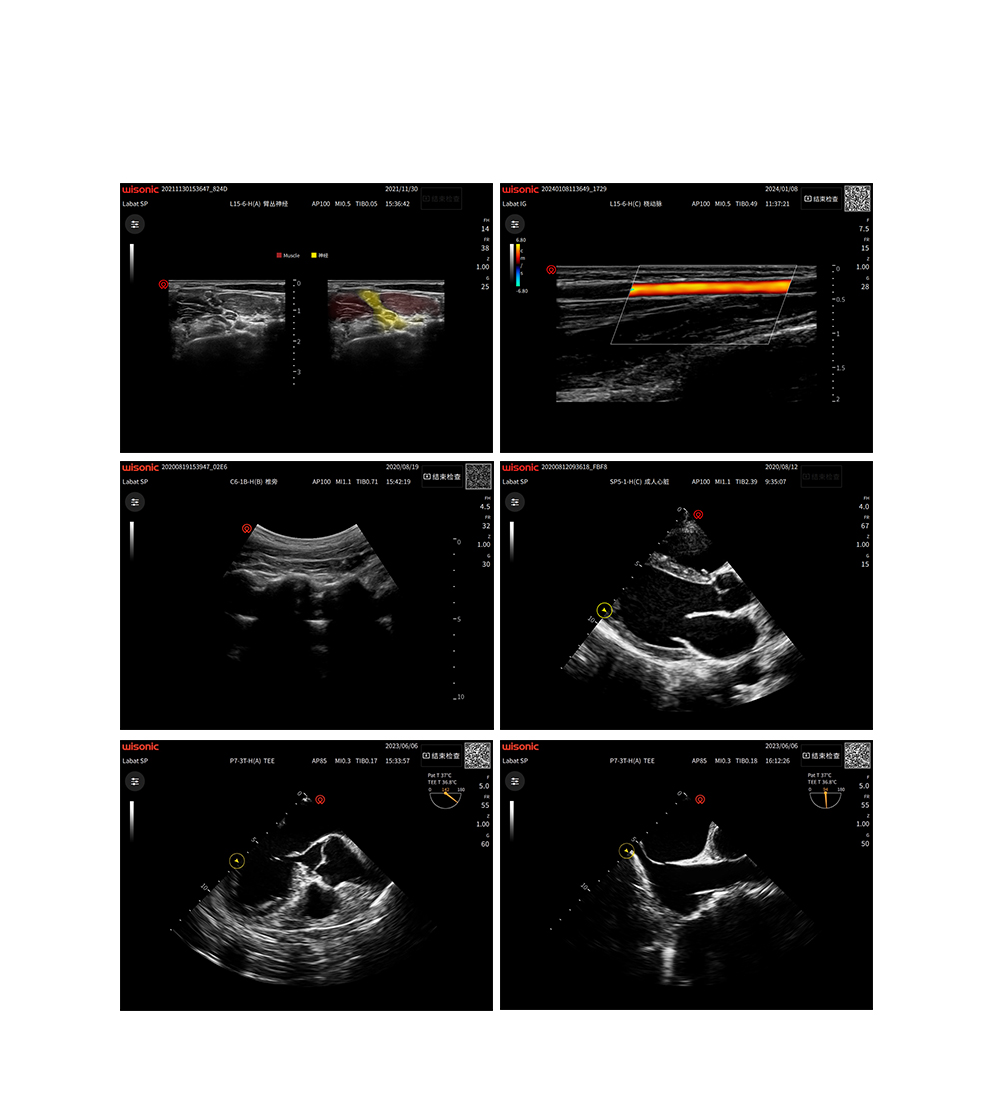

美图鉴赏

临床图片